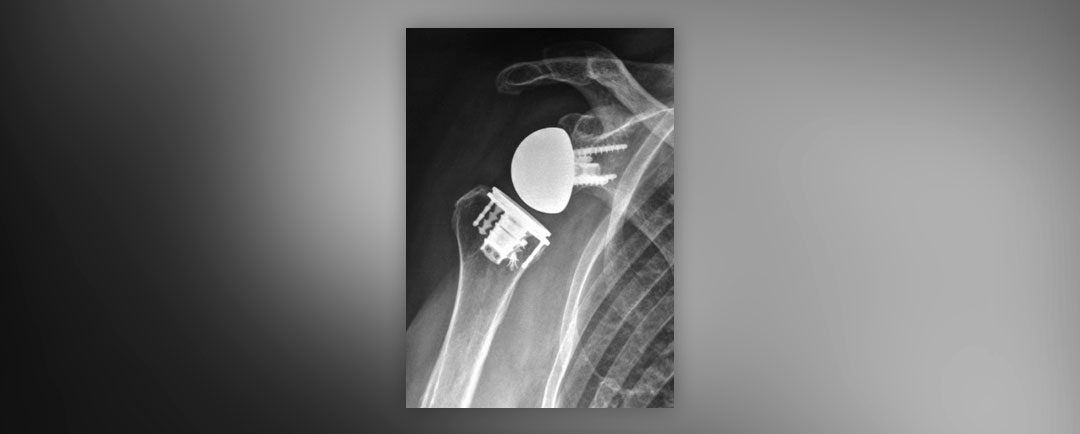

Prótesis de Hombro Invertida Prótesis de Hombro Invertida Prótesis de Hombro Invertida: Se denomina así porque, en su diseño se invierte la anatomía de lo que es un hombro normal, es decir; lo que es “la bola” del hombro pasaría a estar en la escápula y “la cavidad”...